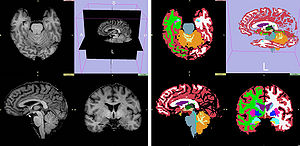

MRI-Only Based Radiotherapy Treatment Planning for the Rat Brain on a Small Animal Radiation Research Platform (SARRP)

Publication: PLoS One. 2015 Dec 3;10(12):e0143821. PMID: 26633302 | PDF Authors: Gutierrez S, Descamps B, Vanhove C. Institution: Medical Image and Signal Processing Group, Ghent University-iMinds Medical IT department, Ghent, Belgium. Background/Purpose: Computed tomography (CT) is the standard imaging modality in radiation therapy treatment planning (RTP). However, magnetic resonance (MR) imaging provides superior soft tissue contrast, increasing the precision of target volume selection. We present MR-only based RTP for a rat brain on a small animal radiation research platform (SARRP) using probabilistic voxel classification with multiple MR sequences. Six rat heads were imaged, each with one CT and five MR sequences. The MR sequences were: T1-weighted, T2-weighted, zero-echo time (ZTE), and two ultra-short echo time sequences with 20 μs (UTE1) and 2 ms (UTE2) echo times. CT data were manually segmented into air, soft tissue, and bone to obtain the RTP reference. Bias field corrected MR images were automatically segmented into the same tissue classes using a fuzzy c-means segmentation algorithm with multiple images as input. Similarities between segmented CT and automatic segmented MR (ASMR) images were evaluated using Dice coefficient. Three ASMR images with high similarity index were used for further RTP. Three beam arrangements were investigated. Dose distributions were compared by analysing dose volume histograms. The highest Dice coefficients were obtained for the ZTE-UTE2 combination and for the T1-UTE1-T2 combination when ZTE was unavailable. Both combinations, along with UTE1-UTE2, often used to generate ASMR images, were used for further RTP. Using 1 beam, MR based RTP underestimated the dose to be delivered to the target (range: 1.4%-7.6%). When more complex beam configurations were used, the calculated dose using the ZTE-UTE2 combination was the most accurate, with 0.7% deviation from CT, compared to 0.8% for T1-UTE1-T2 and 1.7% for UTE1-UTE2. The presented MR-only based workflow for RTP on a SARRP enables both accurate organ delineation and dose calculations using multiple MR sequences. This method can be useful in longitudinal studies where CT's cumulative radiation dose might contribute to the total dose. |

Illustration of a CB-CT and five MR images of the same animal. a) Coronal CB-CT image and (b)-(f) biased field corrected and masked coronal MR images using a T1-weighted (b), T2-weighted (c), ZTE (d), UTE1 (e) and UTE2 (f) sequence. All CB-CT images were first co-registered using 3D Slicer version 3.6.3 by rigid body transformations using normalized mutual information. |